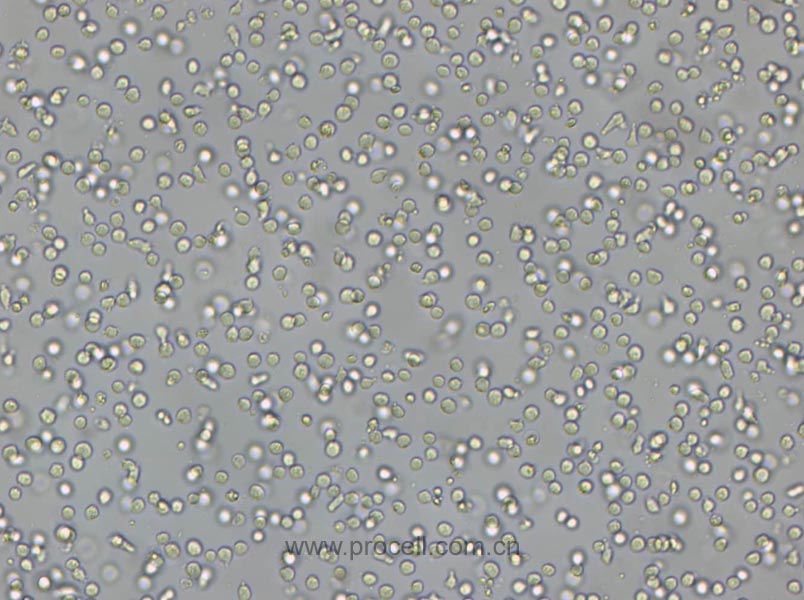

SW 982 [SW-982, SW982] (人滑膜肉瘤細(xì)胞) (STR鑒定正確)

| 細(xì)胞形態(tài) | 混合形 |

| 背景描述 | SW 982 [SW-982, SW982]是由A·Leibovitz在1974年從一位25歲白人女性的纖維肉瘤手術(shù)切片中建立的細(xì)胞株;病理組織學(xué)評價認(rèn)為,建立SW 982 [SW-982, SW982]細(xì)胞株的纖維肉瘤是與脂肪肉瘤一致的未分化惡性腫瘤。 |

| 組織來源 | 組織:滑膜;疾病:滑膜肉瘤 |

| 細(xì)胞類型 | 腫瘤細(xì)胞 |

| 腫瘤類型 | 肉瘤細(xì)胞 |